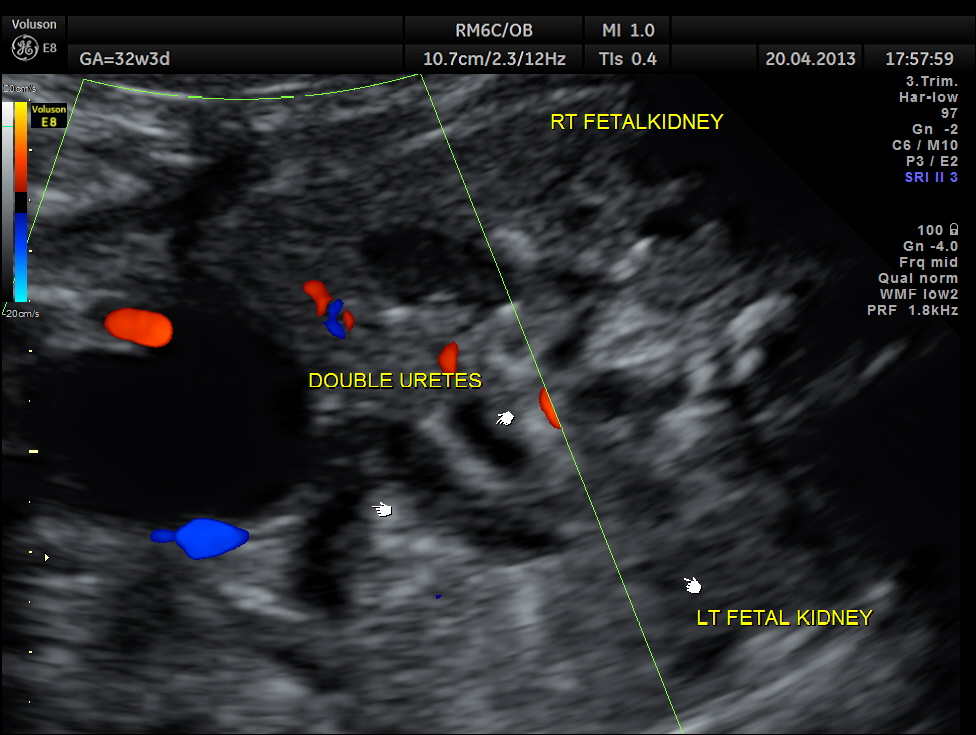

The following images show bilateral renal pelvi ectasis and bilateral dilated ureters with all the changes more in the left kidney .

The left kidney also showed possible duple-ix pelvis with double ureters arising from them . But this finding could not be confirmed in all the views .